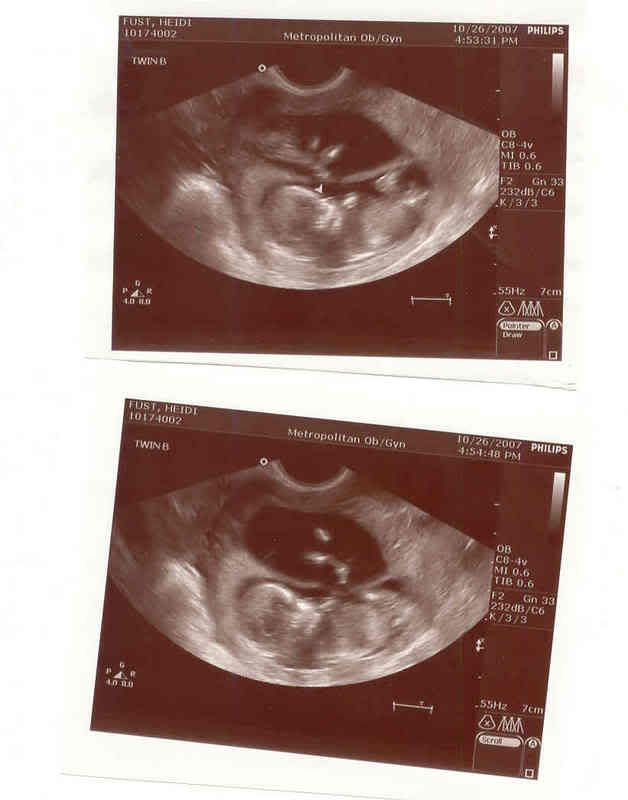

| More baby pictures |

Baby B He/She is looking at the camera in the Second picture. Look at all those teeth buds!!!!